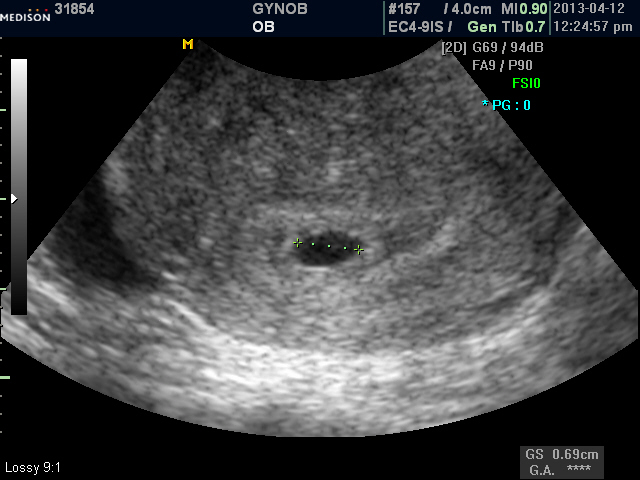

정말 오랫동안 저희와 함께 했는데 이쁜 아가가 찾아 왔네요.. 진심으로 축하드립니다. 며칠 전에 초음파로 아기집을 확인하시고 "선생님, 되었어요.." 하고 저희 손을 잡아 주실 때 정말이지 눈물이 왈칵 쏟아지더군요.. 제가 오히려 고맙다라는 말을 하고 싶었는데.. 오랫동안 포기 하지 않으시고 저희와 함께 해주셔서 감사합니다. 이제 아가 보러 오신다고 생각하니 기분이 한결 더 좋습니다. 태교 잘 하시고 저희 병원에서 이쁜 아가 모습 보여 주세요.. |